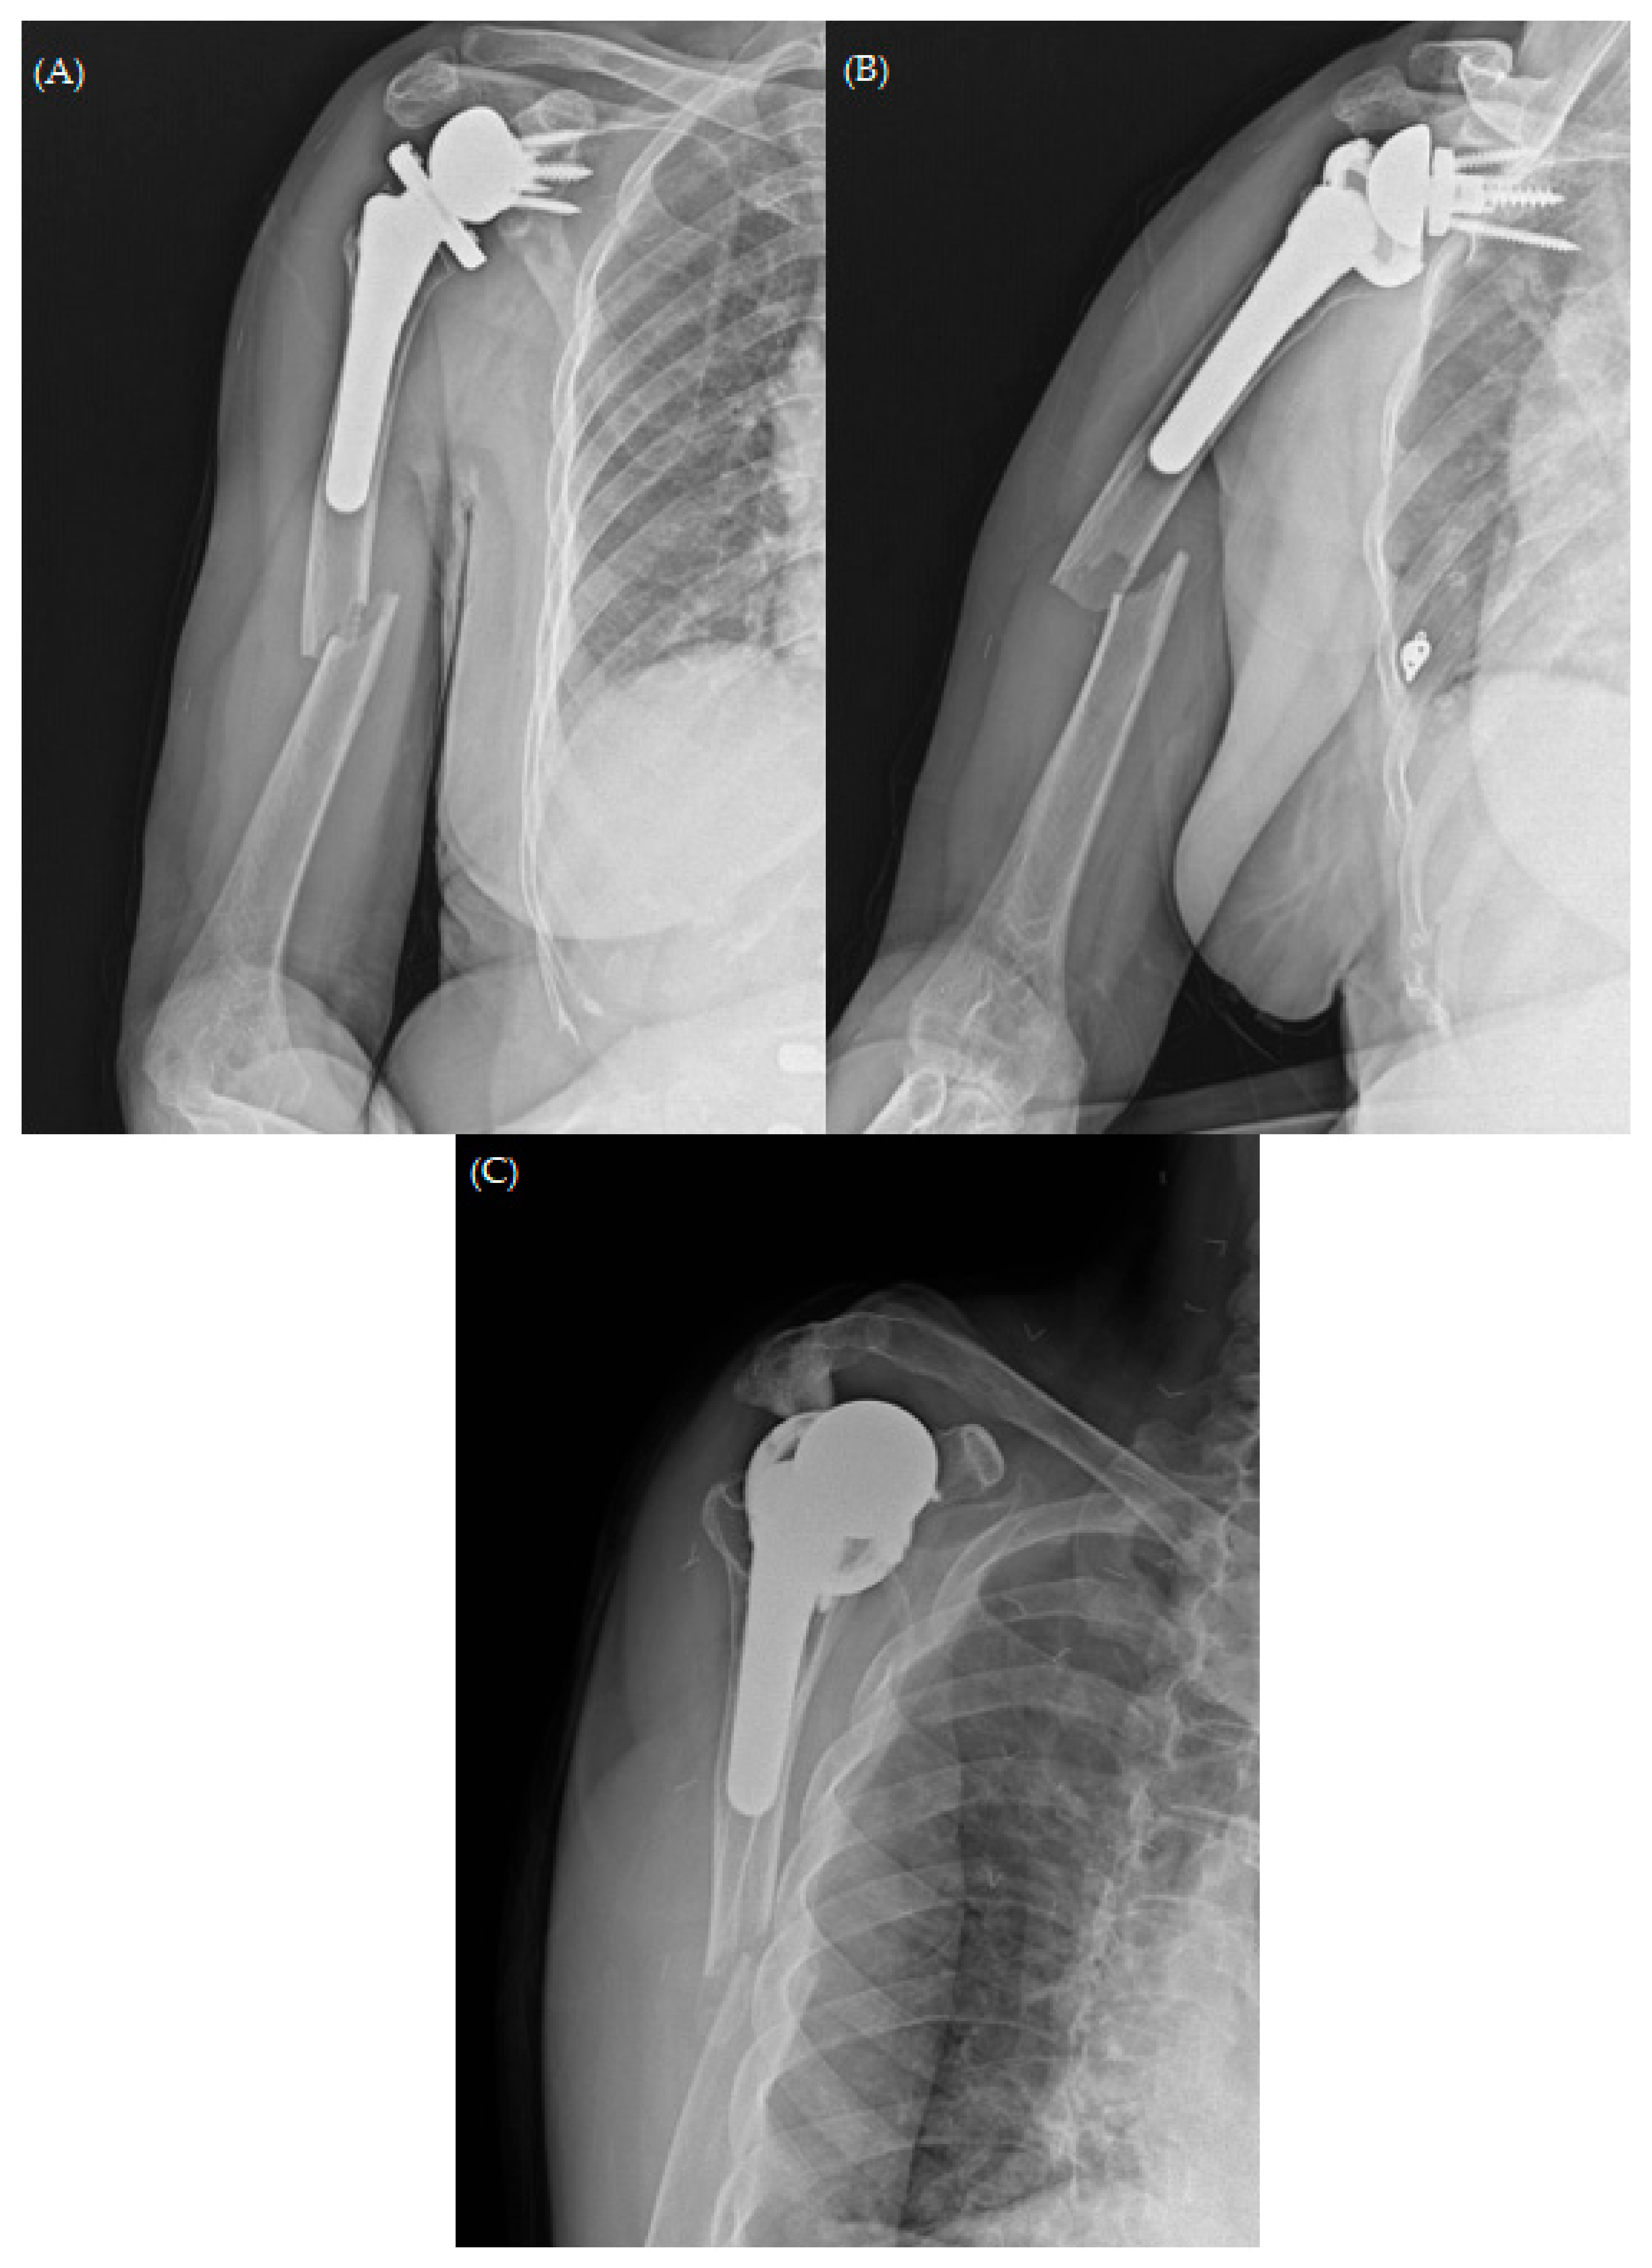

Figure 7. Plain radiographs of humerus (A) AP; (B) lateral and (C,D) oblique views 6 months after revisional open reduction and internal fixation with “bamboo support” structural allograft technique.

The patient returned to our outpatient clinic every two weeks for a general check-up. Her arm was immobilized with a shoulder brace for six weeks. After the initial six weeks post-operation, she was permitted to engage in passive range of motion exercises (including forward flexion, abduction, and internal rotation) with tolerable pain. Any weight-bearing exercise or motions were not allowed until three months post-operation. The fracture healed six months after undergoing revision fracture fixation (Figure 7). She had been working as an office cleaner before the traumatic event and was able to return to work with high satisfaction of her shoulder status. She achieved an ROM of 170° forward flexion, 160° abduction, 40° external rotation, and a second lumbar vertebra level for internal rotation. Her visual analog scale (VAS) score for pain, American Shoulder and Elbow Surgeons (ASES) score, and Subjective Shoulder Value (SSV) score were 0, 85, and 90, respectively.